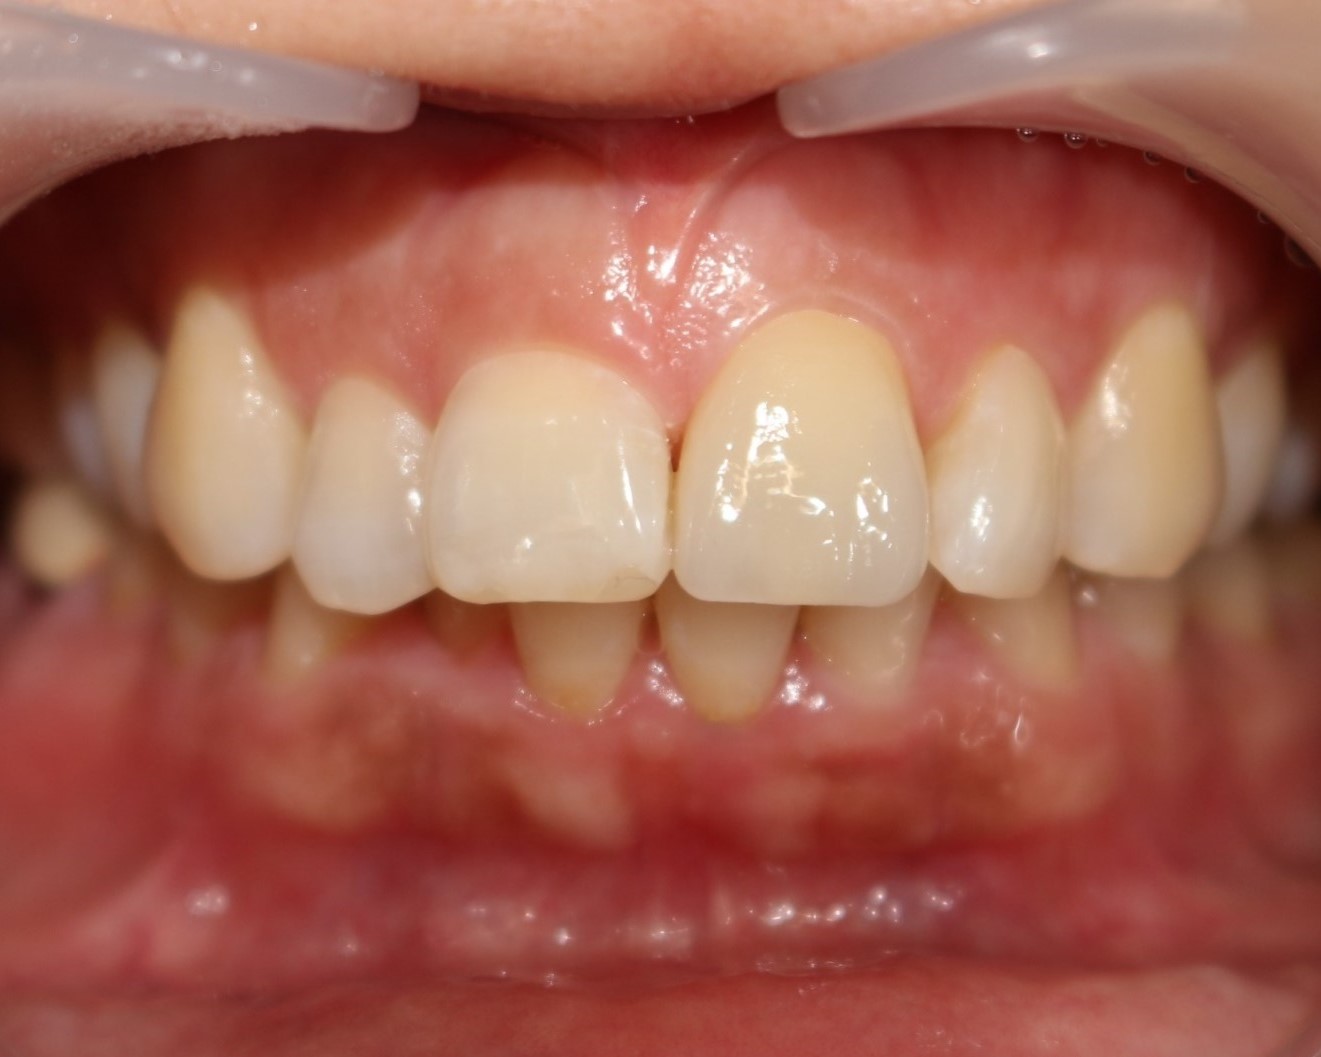

전치부 치아 파절 크라운치료 (PFZ)

전후사진

수술 전

수술 후